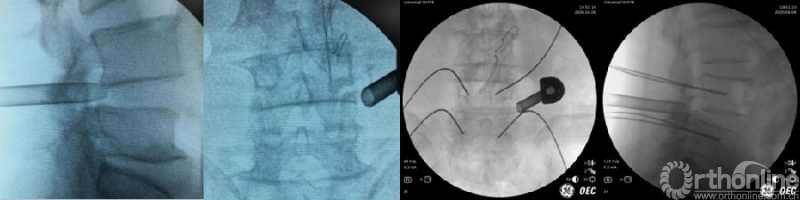

(5)穿刺及导丝置入

无菌消毒,铺无菌巾、单后,根据术前规划及椎弓根体表投影点置入穿刺针,C臂正侧位透视确认穿刺针位置满意。置入导丝,深度进入椎体后缘达椎体中心位置,避免过浅,以免操作过程中导丝滑落。如果先进行减压和融合的话,穿刺针需平行椎间隙置入。

(6)逐层切开及通道放置

沿穿刺针插入导丝,纵行切开皮肤长约1.5cm,逐级扩张皮下、腰背筋膜至关节突关节,放入半齿工作套管或U型工作套管等,C臂再次透视套管位置位于上关节突腹侧,尖端尽力到达椎间盘表面。如果是先置入4枚经皮螺钉导丝的话,则需选择尾侧一枚经皮螺钉切口,适当向头端延长约1.5cm后,平行椎间隙置入工作套管。